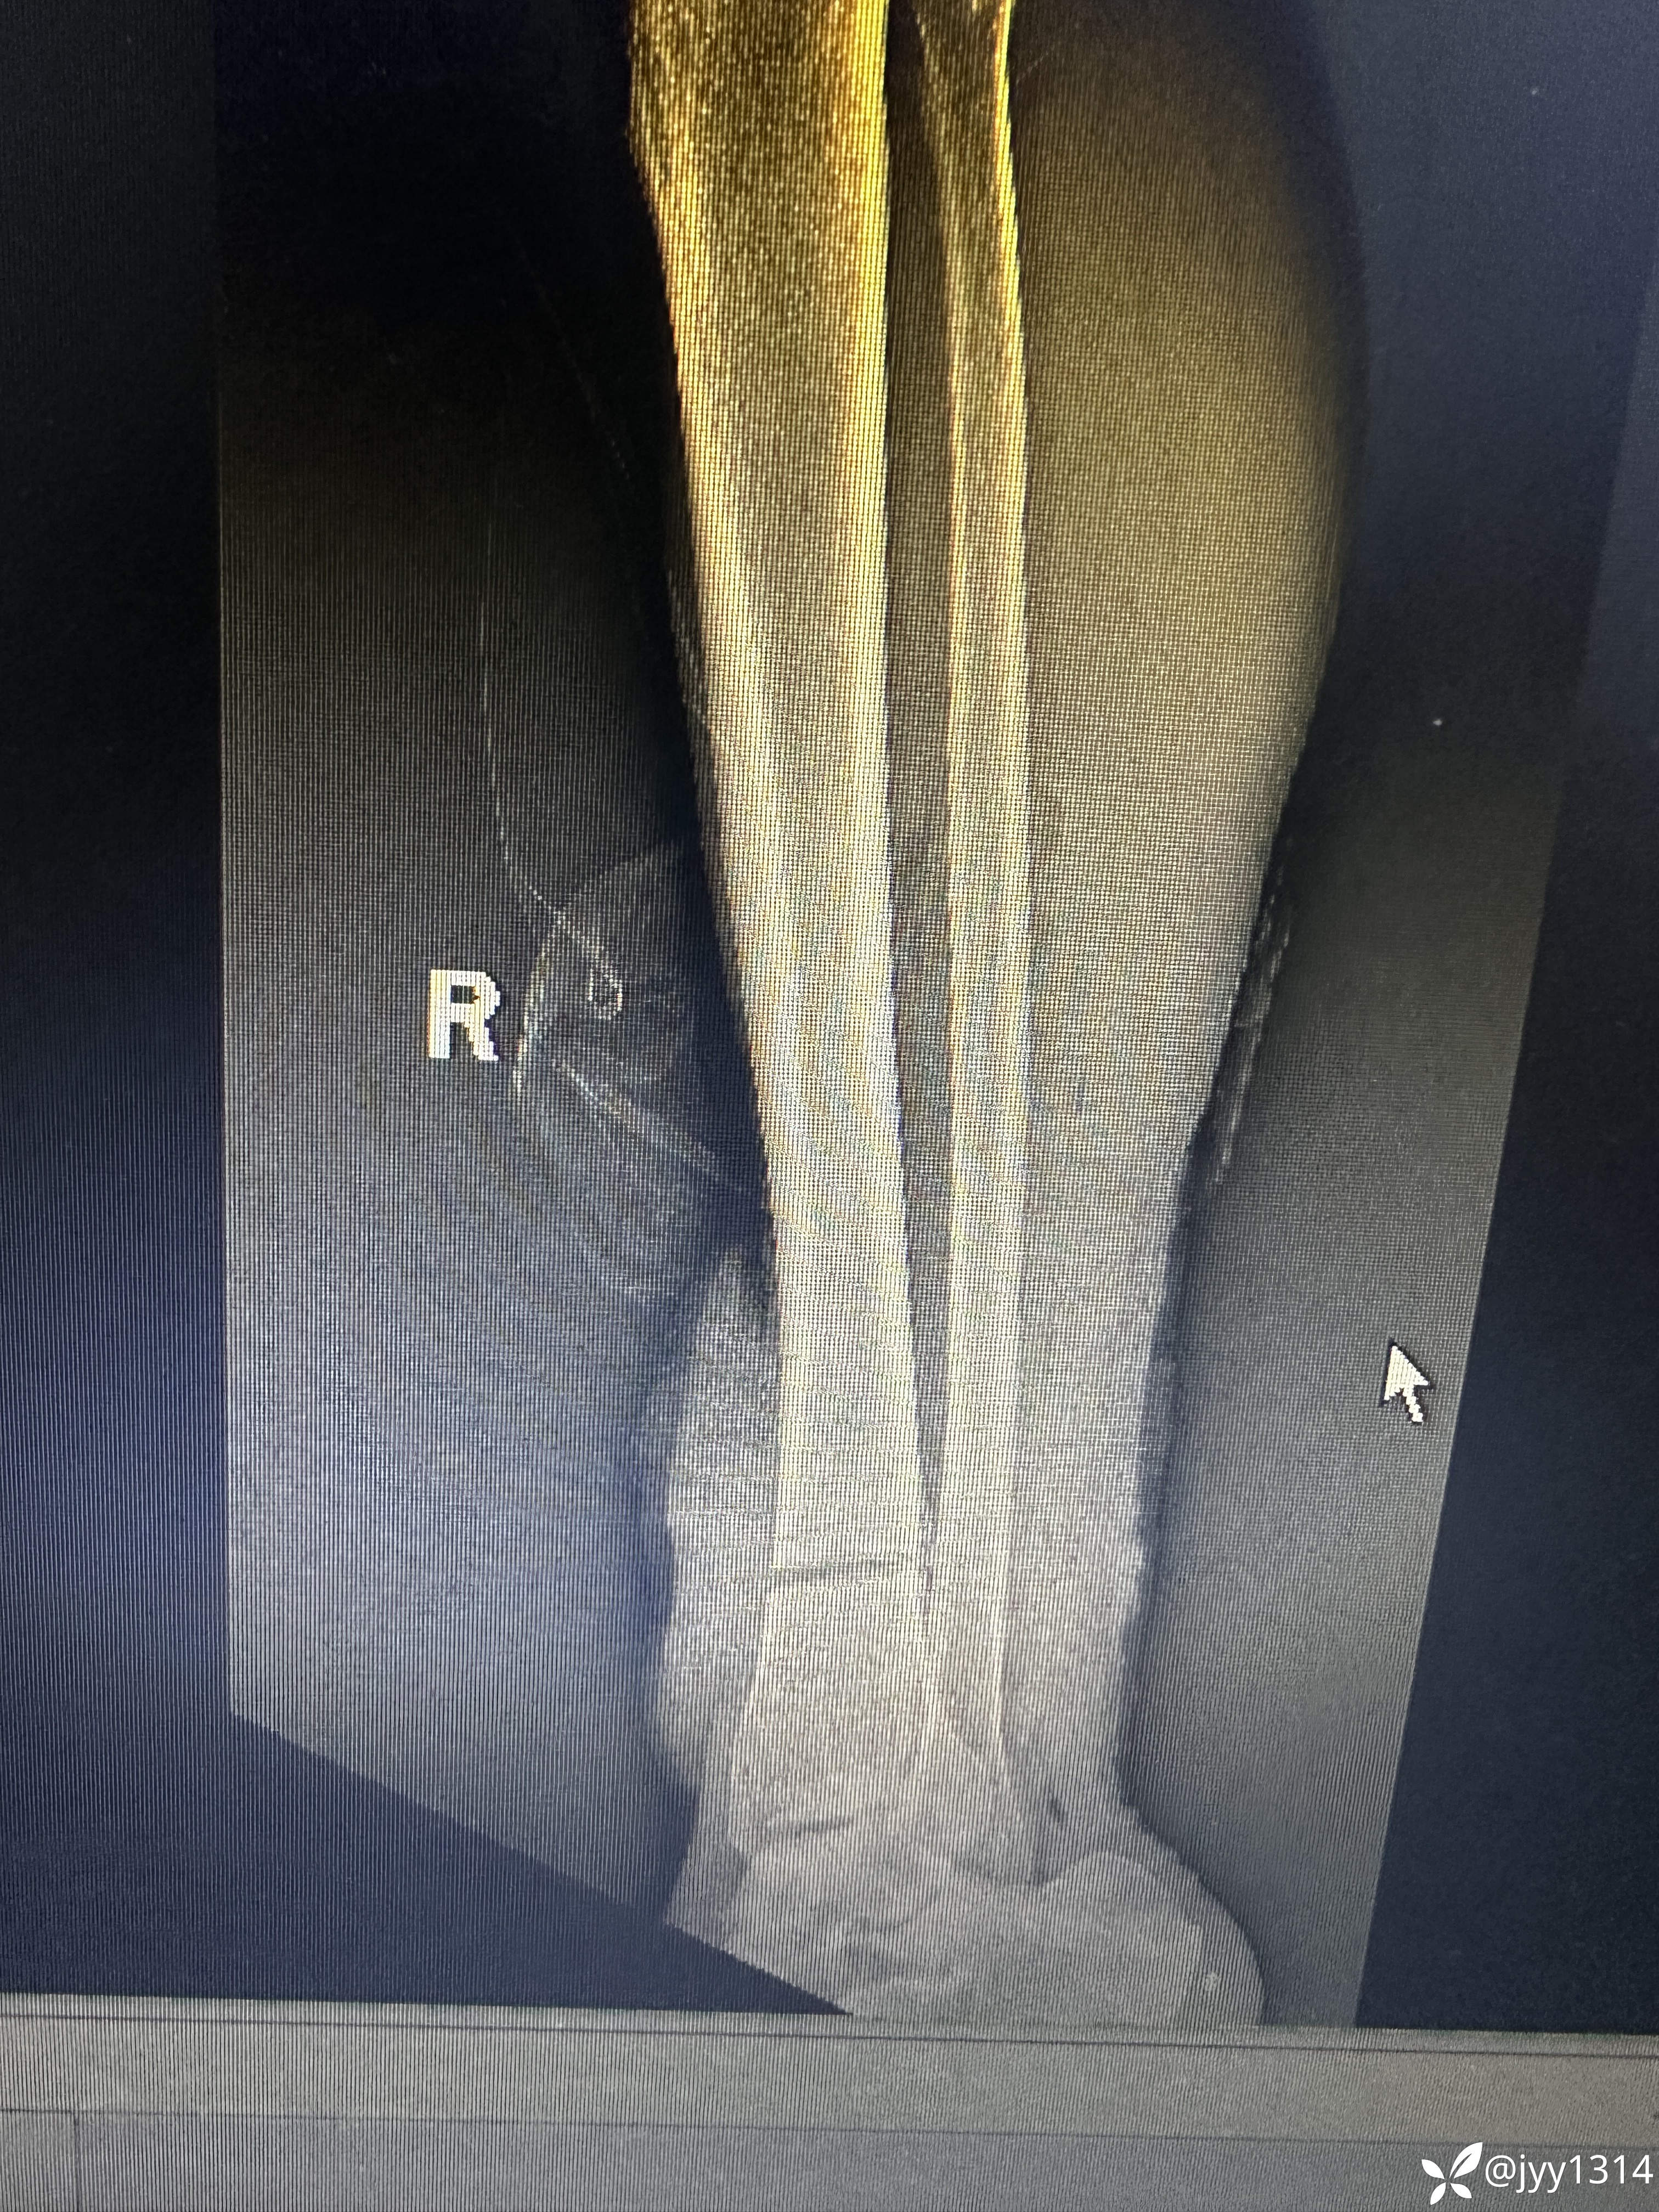

患者 男 63岁,右下肢锯伤1小时余。

患者1小时前与家人争执情绪激动使用电锯锯伤右小腿,致右下肢疼痛、出血,呼叫周围邻居送往我院。神志清,精神欠佳,表情痛苦,大、小未排。

神志清,精神欠佳,面色苍白,头部无压痛,胸部无压痛,心肺未闻及异常,腹软,无压痛,肝脾肋下未触及肿大。右小腿远端可见离断缺口,伤口周围出血不止,右下肢末端皮肤淤青。余肢体未见异常。